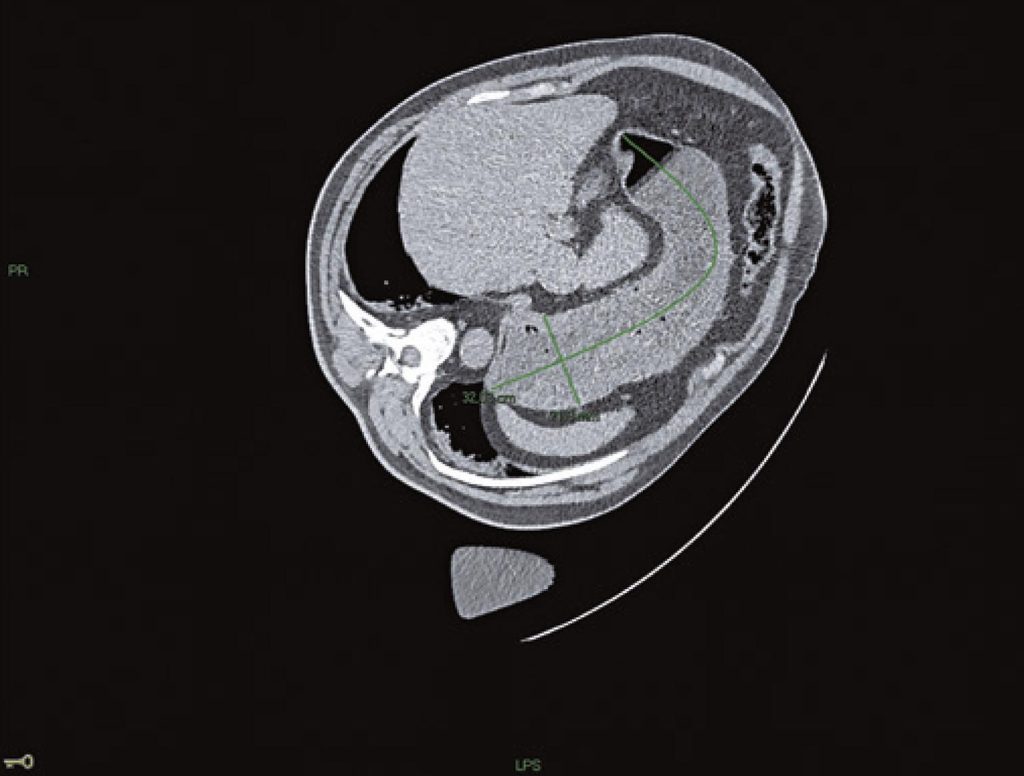

Figure 1 from Management of pulmonary aspiration due to undiagnosed Pulmonary Aspiration Anesthesia pulmonary aspiration was suspected after suctioning fluid from the. although pulmonary aspiration complicating operative general anaesthesia has been extensively studied, little is known regarding. pulmonary aspiration pertains to the inhalation of substances from the oral cavity or upper gastrointestinal tract. The inhalation of oropharyngeal or gastric contents into the larynx and the respiratory tract. perioperative pulmonary. Pulmonary Aspiration Anesthesia.